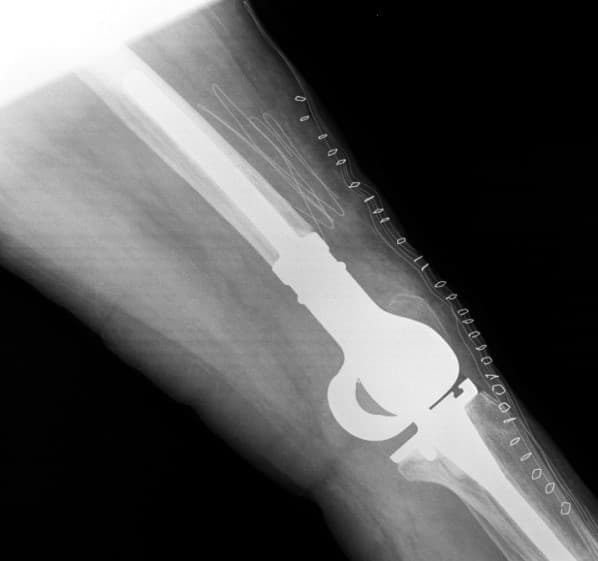

Үе дайрсан ясны анхдагч хавдар, ясны дутмагшлын үед хийгдэх мэс засалimg17Үе дайрсан ясны анхдагч хавдар, ясны дутмагшлын үед хийгдэх мэс засалimg18

Зураг 1. Сэргээн засах мэс заслын өмнөх рентген зураг. Эгц урд, хажуугаас авсан байдал.